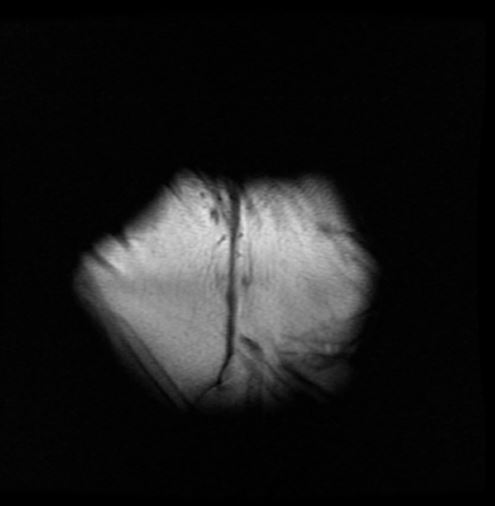

There’s another work in the exhibition, on the other side of the wall from Body and Soul called no other findings. That work uses calibration scans from an MRI machine that appear to be abstract images, but they contain more information than the video behind it. But if you don't understand that language or understand how those machines work, the full context will not be legible. What is legible? What can be translated? I’m interested in how to reflect, deflect and refuse legibility.

Images: |LS|1|RS| Dr. Nehal El-Hadi. Photo by Gillian Mapp. |LS|2|RS| Jessica Karuhanga, no other findings, 2021. Single-channel video. 01:15 mins. |LS|3|RS| Jessica Karuhanga, through a brass channel, 2017. Copper pipe, brass bangle, stone. Photo by Scott Lee. All images courtesy © of Jessica Karuhanga.